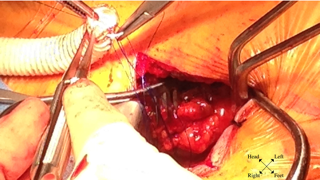

A right parasternal mini-thoracotomy was made. The second costocartilage was removed and the mammary artery was clipped and divided. Upon opening the pericardium, the mid and distal ascending aorta was exposed. The distance from the exposed aorta to the aortic annulus was short, less than the 7.5 cm needed for a 26 mm Sapien valve. A partial cross clamp was placed on the ascending aorta and a 10 mm Hemashield graft was anastomosed to the aortotomy, in an end-to-side fashion, to extend the distance between the aortic annulus and the sheath insertion site (Figures 1 & 2).

Figure 1: Performing 10 mm Hemashield graft end-to-side anastomosis to partially cross-clamped ascending aorta.